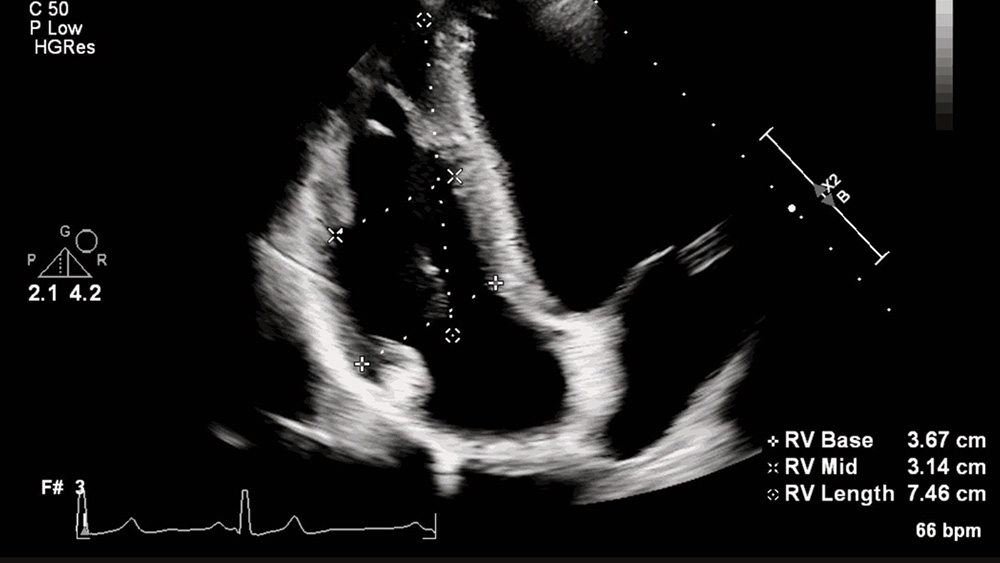

En la atención cardiaca, la ecografía se ha convertido en una herramienta indispensable para ayudar a visualizar y evaluar la función cardiaca del paciente. De hecho, en la actualidad suele ser la primera modalidad de imagen utilizada para diagnosticar a los pacientes [2]. Sin embargo, el reto de la ecografía es que depende en gran medida de la persona que maneja el sistema. Ciertas mediciones, necesarias para cada examen ecográfico, pueden requerir mucho tiempo y presentan una gran variabilidad entre usuarios y dentro de ellos.

Con la IA, podemos eliminar parte de ese trabajo manual y repetitivo, al igual que en algunos de los otros ejemplos de IA en la sanidad de este resumen. Las mediciones automáticas basadas en la IA pueden ofrecer una cuantificación de ecos rápida y reproducible, mejorando la experiencia tanto del paciente como del personal. Los profesionales sanitarios pueden aceptar o modificar las mediciones en función de sus propias evaluaciones clínicas, lo que les proporciona una poderosa herramienta para mejorar su experiencia mientras mantienen el control de la toma de decisiones de diagnóstico.